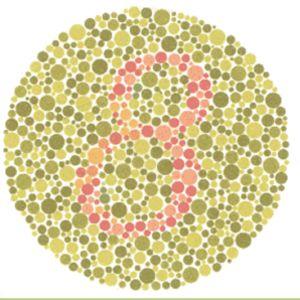

normal de pas voir le 3, faut être daltonien sinon c'est 8

Quand t'es daltonien tu ne voit pas une partie du 8 et du coup tu vois un 3 👀

Comment on peux voir un 3??

C simple , si on est daltonien tu peux voir n'importe quoi !!!

Donc y'a 4% de Daltoniens!

ou 4% de gens qui ont glissé

mais non au contraire, si on voit un 3 on est daltonien, autrement dit un ou certains des cônes visuels ne fonctionnent pas, c'est un désavantage :/

On voit un 3 psk il y a une partie plus claire

Un 8 ça fait un 3 à l' endroit et un 3 à l' envers